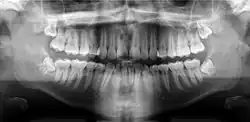

Панорамная рентгенограмма показывает нижние зубы мудрости с горизонтальным ретинированием